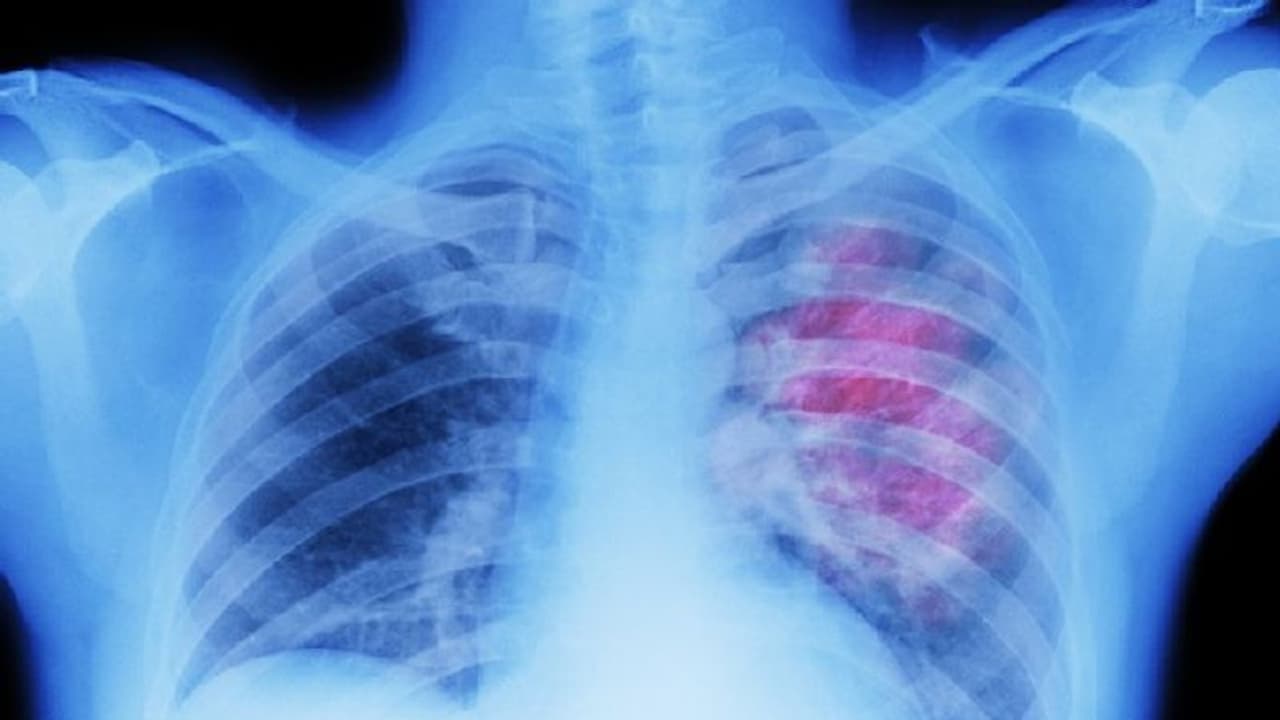

കൊവിഡ് 19 ( Covid 19 Infection )അടിസ്ഥാനപരമായി ഒരു ശ്വാസകോശ രോഗമാണെന്ന് ( Lung Disease ) നമുക്കെല്ലാം അറിയാം. പല അവയവങ്ങളുടെയും പ്രവര്ത്തനത്തെ ഇത് പ്രതികൂലമായി ബാധിക്കാം. എങ്കിലും ഏറ്റവമധികം വെല്ലുവിളി നേരിടുന്നത് ശ്വാസകോശം തന്നെയാണെന്ന് പറയാം.

കൊവിഡ് ബാധയെ തുടര്ന്ന് ന്യുമോണിയ പിടിപെട്ടവര് നിരവധിയാണ്. ഇത്തരത്തില് ന്യുമോണിയ ബാധിക്കപ്പെട്ട് ഗുരുതരാവസ്ഥയിലായവരും തീവ്രപരിചരണ വിഭാഗത്തില് വരെ പ്രവേശിക്കപ്പെട്ടവരും ജീവന് തന്നെ നഷ്ടമായവരും ഉണ്ട്.

ചിലരില് കൊവിഡ് ഭേദമായി ഏതാനും ദിവസങ്ങള്ക്കുള്ളില് തന്നെ ശ്വാസകോശത്തിനേറ്റ പ്രശ്നങ്ങള് ഇല്ലാതായിപ്പോകാം. എന്നാല് മറ്റ് ചിലരില് ഈ പ്രശ്നങ്ങള് ദീര്ഘകാലത്തേക്ക് കിടക്കുകയും മറ്റ് ശ്വാസകോശരോഗങ്ങളിലേക്ക് വഴിവയ്ക്കുകയും ചെയ്യാം. അതിനാല് തന്നെ കൊവിഡ് ശ്വാസകോശത്തെ ബാധിച്ചുവോ ഇല്ലയോ, ഉണ്ടെങ്കില് തന്നെ അതെത്രമാത്രം ഗൗരവമുള്ളതാണ് എന്നെല്ലാം തിരിച്ചറിയേണ്ടത് അത്യാവശ്യമാണ്. ഇതെങ്ങനെയാണ് തിരിച്ചറിയുക?

എന്തായാലും ചുമയും ശ്വാസതടസവും ഒപ്പം തന്നെ താഴ്ന്ന ഓക്സിജന് നിലയും കാണുന്നുവെങ്കില് തീര്ച്ചയായും ഡോക്ടറെ കണ്ട് സിടി സ്കാന് ചെയ്യേണ്ടതുണ്ടോയെന്ന് അന്വേഷിക്കുക. ന്യുമോണിയയുടെ അവശേഷിപ്പുകള് ശ്വാസകോശത്തിലുണ്ടോയെന്ന് മനസിലാക്കാന് സിടി സ്കാന് ഉപകരിക്കും.

കൊവിഡ് 19 ഒരു ശ്വാസകോശരോഗമാണെങ്കില് കൂടി എല്ലായ്പോഴും രോഗിയുടെ ശ്വാസകോശത്തെ ദോഷകരമായി ബാധിക്കണമെന്നില്ല. എന്നാല് നേരത്തേ ഏതെങ്കിലും വിധത്തിലുള്ള ശ്വാസകോശരോഗങ്ങള് ഉള്ളവരാണെങ്കില് പ്രത്യേകം ശ്രദ്ധിക്കുക, കൊവിഡ് നിങ്ങളുടെ രോഗാവസ്ഥയെ തീവ്രമാക്കാം.

80 ശതമാനം കേസുകളിലും കൊവിഡ് ദീര്ഘകാലത്തേക്ക് നീണ്ടുനില്ക്കുന്ന ശ്വാസകോശ പ്രശ്നങ്ങള്ക്ക് കാരണമാകില്ലെന്നാണ് റിപ്പോര്ട്ടുകള് സൂചിപ്പിക്കുന്നത്. അതേസമയം 10 മുതല് 15 ശതമാനം വരെയുള്ള കേസുകളില് താഴ്ന്ന ഓക്സിജന് നിലയും ശ്വാസതടസവും പോലുള്ള പ്രശ്നങ്ങള് നീണ്ടുനില്ക്കുകയും ചെയ്യുന്നു.

ഇത് കൊവിഡ് ശ്വാസകോശത്തെ നല്ലരീതിയില് ബാധിച്ചുവെന്നതാണ് വെളിപ്പെടുത്തുന്നത്. ഇത്തരം കേസുകളില് പിന്നീട് രോഗിയെ വെന്റിലേറ്ററില് പ്രവേശിപ്പിക്കേണ്ടതായ സാഹചര്യവും ഒരുപക്ഷേ ജീവന് തന്നെ നഷ്ടപ്പെടുന്നതുമായ സാഹചര്യവും ഉണ്ടാകാം.